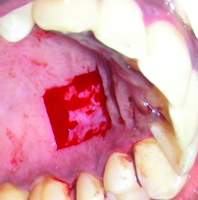

Considering that, it was in the lower anterior region with lack of keratinised tissue, we planned for vestibular deepening with FGG procedure. In the first visit, a thorough full mouth scaling was done, along with root debridement in relation to #41. The patient was given basic oral hygiene instructions with Charter’s method of brushing technique reinforced’ in that area and asked to report after one week. On the second visit, the site was examined and prepared for the surgery. Local anaesthesia was administered at the recipient site; the dimensions of the required graft were mapped using Williams’s periodontal probe and were simulated on a tin foil which was later cut in the shape of the graft to be procured. A horizontal partial thickness incision was placed using “15 number Bard-Parker® blade” at the mucogingival junction of the #41 to dissect the alveolar mucosa from the keratinised tissue, and extended to adjacent one tooth on each side to deepen the vestibule at the recipient site. The keratinised tissue was then de-epithelialised around the root of the lower right central incisor, leaving the interdental papillae intact on each side of the tooth, to expose the underlying connective tissue and to create a trapezoidal recipient bed [Table/Fig-3].

Dental photograph showing de-epithelialisation of the recipient bed around #41.